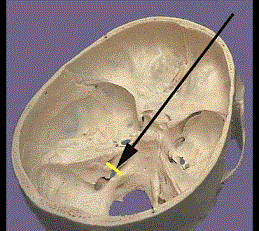

如图箭头所示为哪支脑神经 ( )A、ⅣB、ⅥC、ⅧD、ⅤE、Ⅶ

问题 如图箭头所示为哪支脑神经 ( )

选项 A、Ⅳ B、Ⅵ C、Ⅷ D、Ⅴ E、Ⅶ

答案 C